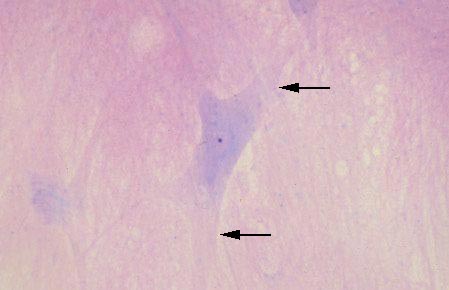

V-2 Spinal Cord Smear (H&E). A neuron (center) is shown with dendrites (arrows), basophilic cytoplasm (Nissl substance), light staining nucleus, and dark staining nucleolus.